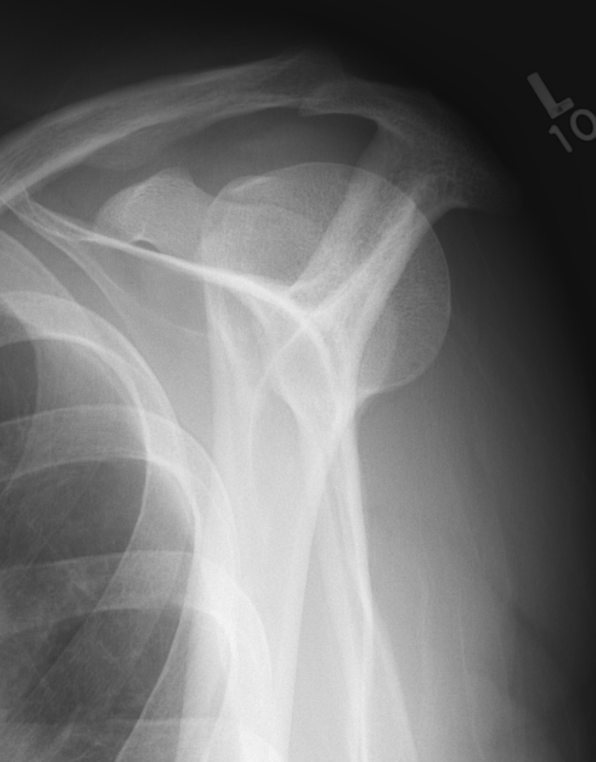

Scapular lateral

Center of the humeral head must be centered on the Y / Mercedes sign

Y is formed by

- coracoid anteriorly

- scapular spine posteriorly

- scapula body inferiorly

Posterior shoulder dislocation